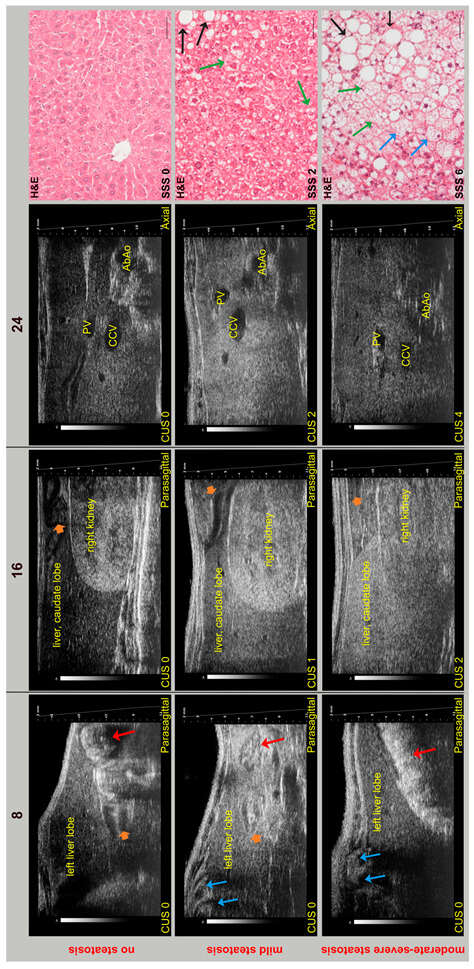

Preclinical Application of Computer-Aided High-Frequency Ultrasound (HFUS) Imaging: A Preliminary Report on the In Vivo Characterization of Hepatic Steatosis Progression in Mouse Models

Metabolic dysfunction-associated steatotic liver disease (MASLD) is one of the most common chronic liver disorders worldwide and can lead to inflammation, fibrosis, and liver cancer. To better understand the impact of an unbalanced hypercaloric diet on liver phenotype in impaired autophagy, the study [...] Read more.

Metabolic dysfunction-associated steatotic liver disease (MASLD) is one of the most common chronic liver disorders worldwide and can lead to inflammation, fibrosis, and liver cancer. To better understand the impact of an unbalanced hypercaloric diet on liver phenotype in impaired autophagy, the study compared C57BL/6J wild type (WT) and MAPK15-ERK8 knockout (KO) male mice with C57BL/6J background fed for 17 weeks with “Western-type” (WD) or standard diet (SD). Liver features were monitored in vivo by high-frequency ultrasound (HFUS) using a semi-quantitative and parametric assessment of pathological changes in the parenchyma complemented by computer-aided diagnosis (CAD) methods. Liver histology was considered the reference standard. WD induced liver steatosis in both genotypes, although KO mice showed more pronounced dietary effects than WT mice. Overall, HFUS reliably detected steatosis-related parenchymal changes over time in the two mouse genotypes examined, consistent with histology. Furthermore, this study demonstrated the feasibility of extracting quantitative features from conventional B-mode ultrasound images of the liver in murine models at early clinical stages of MASLD using a computationally efficient and vendor-independent CAD method. This approach may contribute to the non-invasive characterization of genetically engineered mouse models of MASLD according to the principles of replacement, reduction, and refinement (3Rs), with interesting translational implications. Full article